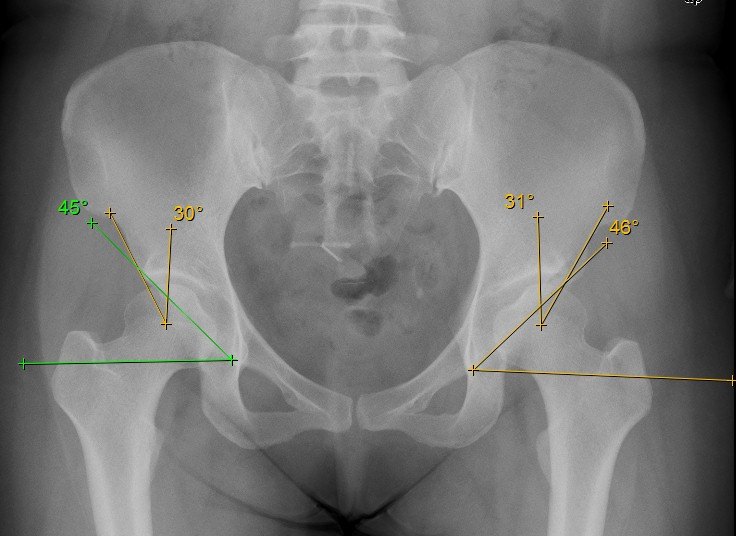

石X,女性,38岁,主诉:左髋反复间断疼痛半年余. 半年前长时间行走出现左髋酸痛不适感,呈间歇性刺痛,位于髋关节深部,休息5-10分钟可缓解,无关节弹响,无绞锁,无下肢放射疼痛及麻木。未予以特别处理。之后左髋经常出现行走酸胀感,活动后加重,症状无法缓解来就诊。查体: 正常步态;屈髋疼痛(+), 腹股沟区压痛(-),大转子压痛(-),ROM:屈髋/后伸/外展/外旋/内收/内旋 110/10/40/30/30/20, FAIR(+), FAER(-),4字征(-),贴床面(2拳), 余(—)。

术前检查 X线 CT和单髋MRI

X线、CT检查能排除髋关节退变、发育不良、骨关节炎、髋关节撞击等骨性异常结构,但不能很好显示软组织病变,因此不能诊断髋臼盂唇损伤。MR检查具有较好的软组织对比性,分辨率较高,可多方位和多序列的成像,可以直接显示髋臼盂唇的形态和信号。MR检查又有MRI(MR Imaging)和MRA(MR Arthrography)之分,后者又可分为直接关节造影(Direct MR Arthrography )和间接关节造影(Idirect MR Arthrography)。